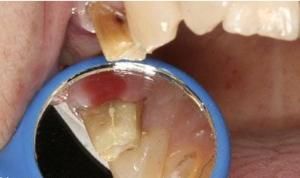

若患牙存在大面積充填物,應首先去除原充填物以評估隱裂的程度、牙髓的狀況和剩餘牙體組織結構。冷刺激的高度敏感及咬物實驗的陽性即可對牙隱裂做出診斷。臨床中常用的方法還包括藉助光纖透照、口內拍照及放大鏡(×16)增強裂紋的可視化來輔助探查。手術顯微鏡的套用也可用來輔助隱裂牙的診斷和治療。有學者推薦使用龍膽紫和亞甲基藍進行可疑牙的染色,但此方法需要較長的時間(至少2~5d)才能起作用,且可能需要戴臨時冠,臨床使用較少。

牙合面可見到裂紋貫通1-2個邊緣嵴而達鄰面,常與發育溝重疊。塗以碘酊液可見其滲入隱裂,顯示清楚為一裂隙。患牙可有冷、熱激發痛,或自發痛等症狀,應仔細檢查,避免漏診。